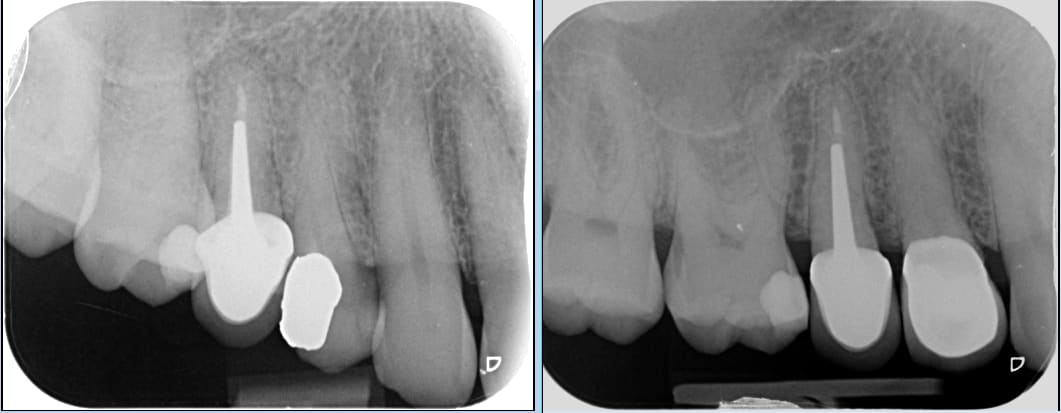

regarde la, fracture du pan vestibulaire...

J'ai fait dépose AG + compo sous digue

Taille empreinte prov sur dent vivante

le patient a choisi une CCM RAC 0 sinon j'aurais collé une Emax.

> le patient a choisi une CCM RAC 0 sinon j'aurais collé une Emax.

Pas de soucis de sensibilités . Ciment prov OZN eugenol . ?

> Pas de soucis de sensibilités . Ciment prov OZN eugenol . ?

Oui tempbond a l eugenol.

Test froid positif...

Pas de carie... Percussion ok et radio ok.

Le plomb qui a 20 ans...

Pour être sûr j ai déposé l AG sans anesthésie... Bon la dent était bien vivante :)))

Après les précautions sur dent vivante... Fraise neuve turbine spray abondant et toilette des surfaces dentinaires au dakin.